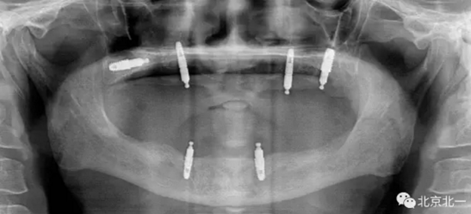

圖一:球帽覆蓋義齒

1.png

圖二:覆蓋義齒

2.png

圖三:植體負(fù)重一年后脫落掉入上頜竇,

3.png

圖四:王明老師接手時植體往后移位,

4.png